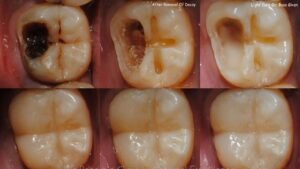

इस बारे में हमने खुल्बे डेंटल केयर एंड इम्प्लांट सेंटर की डेंटिस्ट डॉ. तेजस्वी भट्ट खुल्बे (गोल्ड मेडलिस्ट) से बात की। उन्होंने बताया कि दांत में कीड़ा लगना दरअसल बैक्टीरियल संक्रमण के कारण दांत में छेद (कैविटी) बनने की प्रक्रिया है। यह काला धब्बा छोटे से शुरू होकर दांत की नस तक पहुंच सकता है। यदि समय पर इलाज न कराया जाए तो इसके कारण तेज दर्द, संवेदनशीलता बढ़ना और दांत टूटने जैसी गंभीर समस्याएं हो सकती हैं।

कैविटी बनने के बाद कोई भी घरेलू उपाय इसे ठीक नहीं कर सकता क्योंकि यह अंदर से सड़ी हुई और संक्रमित होती है। इसे केवल डेंटिस्ट की मदद से ही सही तरीके से साफ किया जा सकता है। डॉक्टर एक खास उपकरण से दांत के सड़े हुए हिस्से और उसमें मौजूद बैक्टीरिया को पूरी तरह साफ करते हैं। इसके बाद दांत में बने छोटे छेद को कंपोज़िट मटेरियल से भर दिया जाता है, जिसे फिलिंग कहते हैं। फिलिंग करवाने से दांत मजबूत हो जाता है, कैविटी बढ़ना रुक जाता है, दर्द बंद हो जाता है और दांत फिर से सड़ने से बच जाता है।